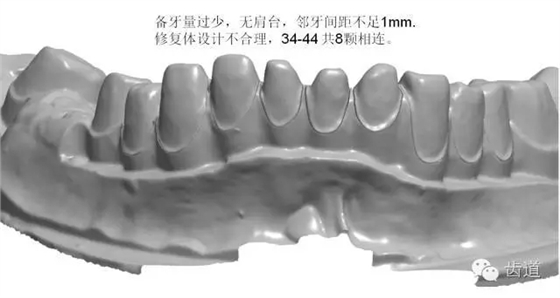

如:無肩臺、凹面肩臺、邊緣線不清晰、雙重邊緣線、備牙空間不足、基牙有倒凹或牙橋沒有共同就位道、基牙切端或頜緣過于尖銳等等。

解決方案:按要求制備基牙 1.將基牙預(yù)備成圓緩的斜面肩或軸-頸線角圓鈍的水平直角肩臺,建議制備肩臺寬度為0.5~1.0mm。 2.咬頜面和切端需磨除0.8~1.5mm,軸面聚合角度為3°~6°,軸壁與咬頜面的連接處應(yīng)圓鈍,轉(zhuǎn)角半徑大于0.5mm. 3.頜面120°~140°的開放角度可以保證在切削過程中精確的復(fù)制出內(nèi)冠的表面,進而達到完好的密合。 4.連橋制備時要求基牙間具有共同就位道,避免倒凹。